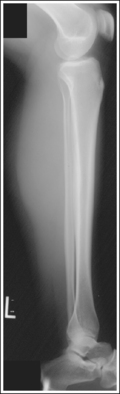

The distal and proximal ends of the fibula are superimposed by the tibia, whereas the fibular midshaft is free of superimposition. The knee is flexed approximately 45 degrees, and the femoral condyles are superimposed.

No corrective movement is required, although knee flexion may result in elevation of the proximal lower leg and foreshortening of the tibia and fibula.